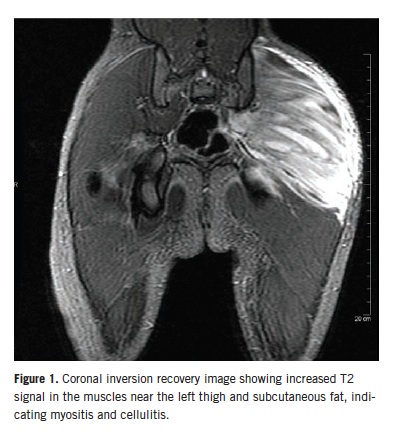

An ultrasonogram of the hip showed edema around the hip joint but no effusion. Magnetic resonance imaging (MRI) revealed findings consistent with extensive myositis involving multiple left hip muscles, as well as pyomyositis with associated intramuscular abscesses involving the left gluteus maximus muscle (Figures 1 and 2). There was no evidence of septic arthritis or osteomyelitis. The patient was started on a regimen of intravenous clindamycin and vancomycin.